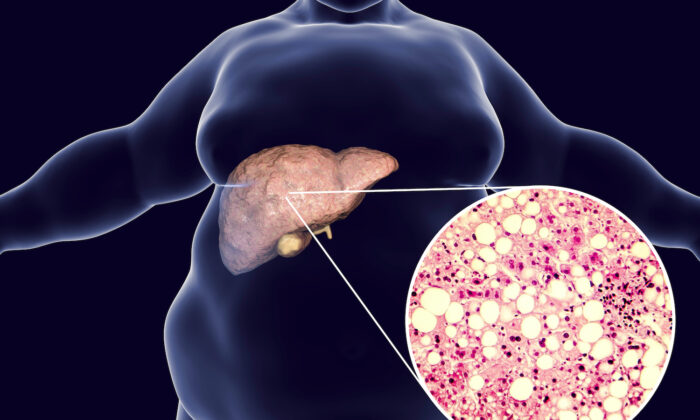

Viêm gan mỡ không do rượu (NASH) xảy ra trên người uống ít rượu hoặc không uống rượu, khi chất béo tích tụ trong gan.

Các yếu tố nguy cơ cao bị bệnh gan nhiễm mỡ không do rượu bao gồm tiểu đường, cholesterol cao, chất béo trung tính cao, ăn uống kém dinh dưỡng, hội chứng chuyển hóa, hội chứng buồng trứng đa nang, chứng ngưng thở khi ngủ và suy tuyến giáp.

Viêm gan gây ra NASH, dẫn đến tích tụ chất béo trong mô gan và hình thành mô sẹo, mô sẹo lâu ngày có nguy cơ tiến triển thành xơ gan – căn bệnh nặng có thể đe dọa tính mạng.